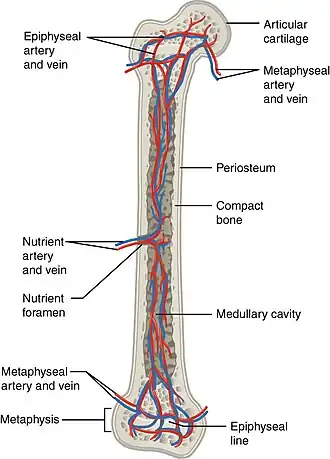

The blood supply to long bones, here with nutrient artery, vein and foramen labeled. | |

All bones possess larger or smaller foramina (openings) for the entrance of blood-vessels; these are known as the nutrient foramina, and are particularly large in the shafts of the larger long bones, where they lead into a nutrient canal, which extends into the medullary cavity. The nutrient canal (foramen) is directed away from the growing end of bone. The growing ends of bones in upper limb are upper end of humerus and lower ends of radius and ulna. In lower limb, the lower end of femur and upper end of tibia are the growing ends.[1] The nutrient arteries along with nutrient veins pass through this canal. A nutrient canal is found in long bones, in the mandible, and in dental alveoli.[2] In long bones the nutrient canal is found in the shaft.